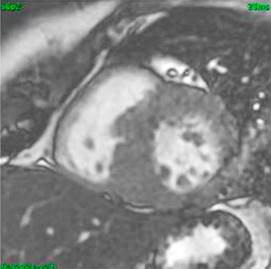

Caso clínico 1: mujer de 41 años, originaria de la Ciudad de México. Sin antecedentes hereditarios de relevancia. Historia de hipertensión arterial sistémica de 12 años de diagnóstico en tratamiento con bisoprolol 5 mg cada 12 horas. Fue sometida a procedimiento quirúrgico por el antecedente de fistula de líquido cefalorraquídeo recidivante. En el seguimiento clínico por cardiología, se realiza resonancia magnética cardiovascular con los siguientes hallazgos en el ventrículo izquierdo: hipertrofia septal asimétrica con grosor máximo de 24.7 mm, a nivel medio 23 mm, pared posterior del ventrículo izquierdo 8 mm, Diámetro diastólico del ventrículo izquierdo de 46 mm, diámetro sistólico del ventrículo izquierdo de 24 mm, con índice de volumen telediastólico de 85.4 mL/m2, e índice de volumen telesistólico de 19.3 mL/m2, la masa miocárdica de es de 212 g, con fracción de acortamiento de 48% y fracción de eyección de 77%. Ventrículo derecho, aurículas y válvulas sin alteraciones morfológicas o funcionales, con diagnóstico de cardiopatía hipertrófica septal asimétrica obstructiva (Figura 1).

Figura 1: Cardiorresonancia magnética del caso clínico 1. Corte transversal con evidencia de hipertrofia septal asimétrica.